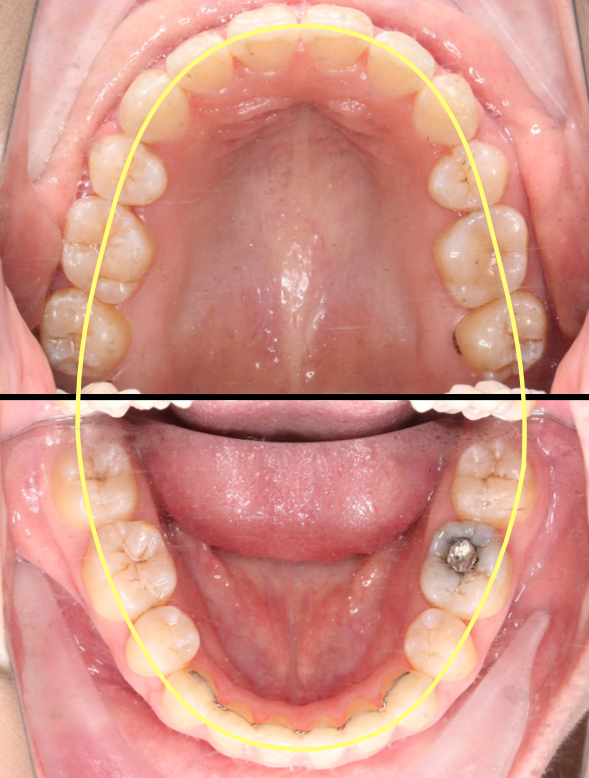

2018.11.14  术后磨牙尖牙I类关系,中线齐,覆合,覆盖正常

牙根基本平行,未见牙根吸收

10 M after Post-Tx

10 M after Post-Tr

2019.08.06  术后  10个月复查